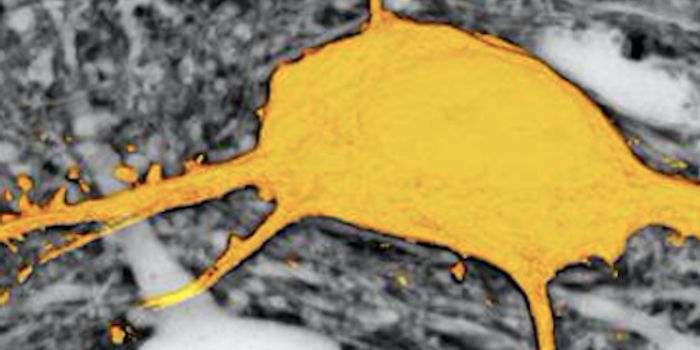

Read the latest articles about newly released neuroscience research and advances in experimental techniques. Topics include research news in neuroscience, neurology, psychology, brain science and cognitive sciences.